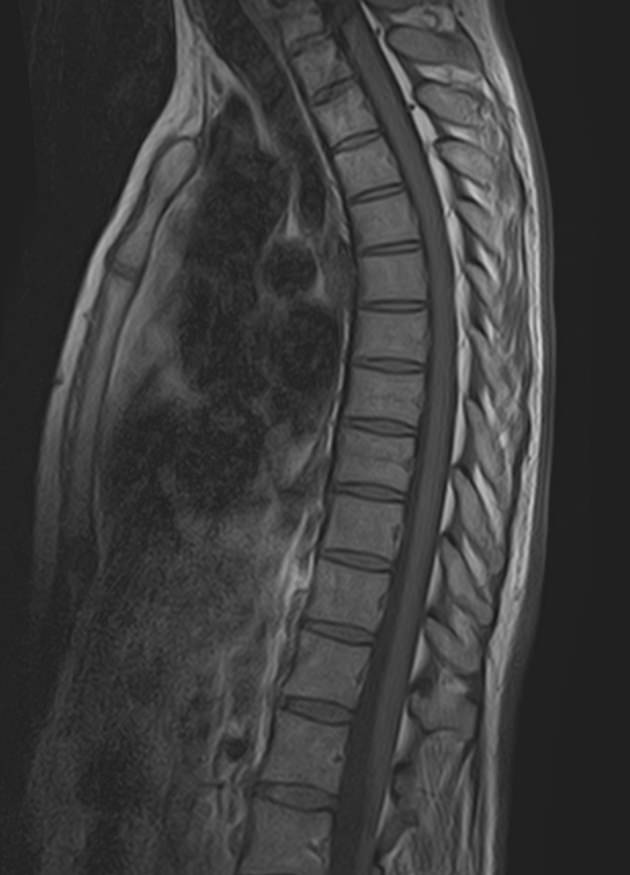

МРТ является современным высокоточным исследованием грудного отдела позвоночника, с помощью которого можно диагностировать различные заболевания, в том числе воспалительные, дегенеративные и опухолевые процессы. Преимуществом данного метода является его безопасность (отсутствие рентгеновского излучения), безболезненность, неинвазивность, при этом высокая информативность.

Клиника «Доступная медицина» оснащена новейшим томографом экспертного класса TOSHIBA VANTAGE TITAN 1,5 Тесла, который позволяет получать превосходные изображения с мельчайшей детализацией всех структур исследуемой области. Это позволяет ставить точный диагноз и выявлять различные заболевания позвоночника на самой ранней стадии.

С помощью МРТ грудного отдела выявляют следующие заболевания позвоночника:

• новообразования;

• степень повреждения спинного мозга в случае переломов тел позвонков;

• грыжи Шморля;

• травматические повреждения тел позвонков и остистых отростков (трещины, переломы, смещения и пр.) — при недоступности КТ;

• разрывы, растяжения связок;

• травмы спинного мозга, нервных корешков;

• протрузии;

• грыжи межпозвонковых дисков;

• остеохондроз позвоночника;

• стеноз спинномозгового канала;

• сосудистые патологии;

• остеомиелит, спондилодисцит;

• рассеянный склероз;

• спондилоартроз;

• спондилез.